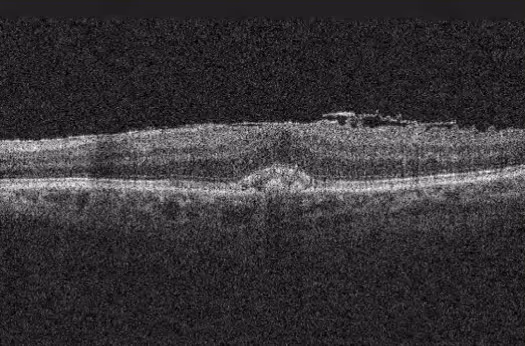

O nevus de coroide é uma lesão pigmentada benigna da camada vascular do olho — uma espécie de 'pinta' no fundo do olho. Quase sempre é inofensivo e descoberto por acaso em um exame de rotina, mas exige acompanhamento porque uma pequena parcela pode se transformar em melanoma de coroide. Entenda a diferença entre nevus, melanocitoma e melanoma, e como o oftalmologista acompanha essas lesões.